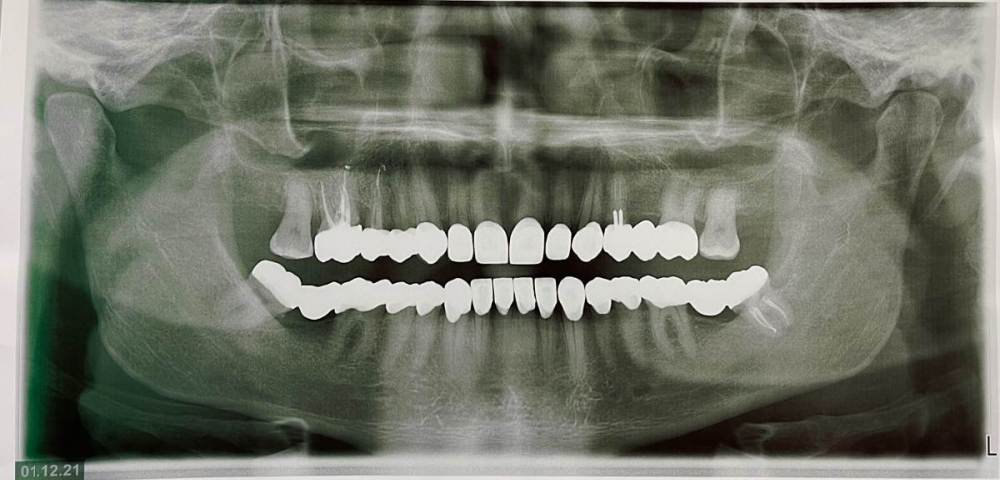

chervoncevdaniil Опубликовано 15 декабря, 2021 Поделиться Опубликовано 15 декабря, 2021 (изменено) Судя по представленным ОПТГ и внутриротовым фото работа сделана на хорошем уровне. По поводу прикуса,по фото его оценить невозможно,потому что непонятно от какого состояния начинали,что иенно меняли и тд. Я бы не торопился и продолжал бы наблюдатся у доктора,который эту работу делал. На временных коронках проблемы с прикусом былм какие то и временные были так же по новому прикусу с закрытием и 8 зубов на НЧ? Изменено 15 декабря, 2021 пользователем chervoncevdaniil 1 Ссылка на комментарий